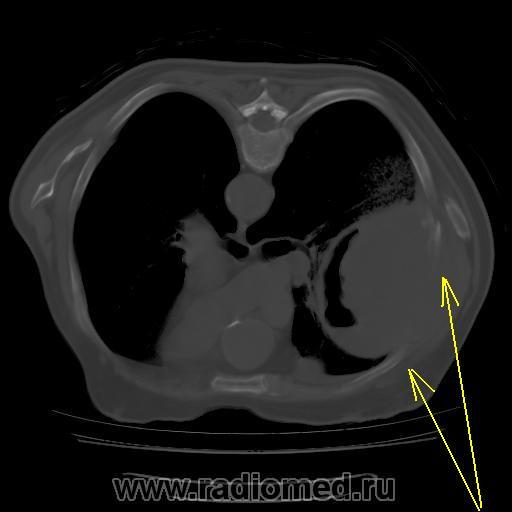

Правое легкое: в проекции средней доли (S3,4,5) определяется объемное образование преимущественно однородной структуры с ровными, четкми контурами размерами 92х88х94мм. Плотность его составляет 19-25 едН. В медиальных отделах образования содержится серповидная полоска воздуха. Латеральные отделы образования выходят за контуры грудной полости на 42 мм. На этом участке ребра не дифференцируются. Внутренний контур передней зубчатой, подлопаточной мышц размытый, граница между образованием и ними отчетливо не видна. Кзади от образования, в кортикальных отделах в легочной ткани инфильтрация. Кпереди от описанного образования расположен участок, широким основанием прилежащий к грудной стенке, имеющий плотность 12-20 ед.Н, однородную структуру, размеры 14х48мм. Прилежащее ребро интактно.

Понятно, что сиреневой стрелкой обозначен "парапроцесс". А вот, что обозначено зелеными стрелками? Для меня это вопрос.

И возникла совершенно шальная мысль. А где располагается "ЭТО"? В легочной ткани или нет? и умозрительное продолжение контуров "ЭТОГО", показало, что "ЭТО" выходит за пределы грудной клетки, а именно костных её компонентов, что находит подтверждение на отдельных сканнах.

А не экстраплевральная - ли "ЭТО" пломба, которая была применена по типу "олеоторакса"?